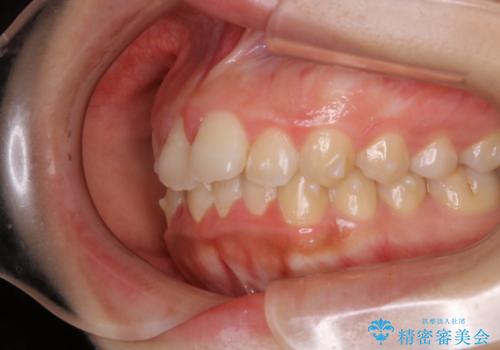

- 20代女性

- ワイヤー審美装置

- 7ヶ月

- 4年ほど前から地元の歯科医院にてインビザライン治療を行っていたが、引っ越し後に通いづらくなってしまったため、治療が途中で止まってしまっているとの事で来院されました。性格的にインビザラインの継続した使用が難しいとのことで、ワイヤー装置にて最終仕上げを行いました。

インビザラインは20時間以上の装着を厳守して頂くことで治療効果が期待できる治療となります。固定式のワイヤー装置に切り替えることで短期間で歯並びを整えることができ、大変喜んでいただけました。